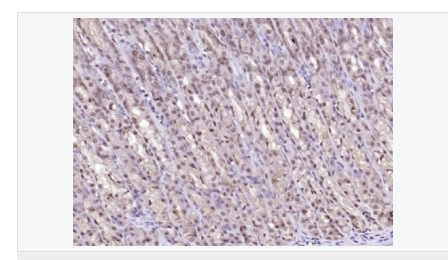

交叉反應(yīng):Human,Mouse,Rat(predicted:Dog,Pig,Cow) 推薦應(yīng)用:WB,IHC-P,IHC-F,ICC,IF,ELISA

產(chǎn)品應(yīng)用WB=1:500-2000 ELISA=1:5000-10000 IHC-P=1:100-500 IHC-F=1:100-500 ICC=1:100-500 IF=1:100-500 (石蠟切片需做抗原修復)